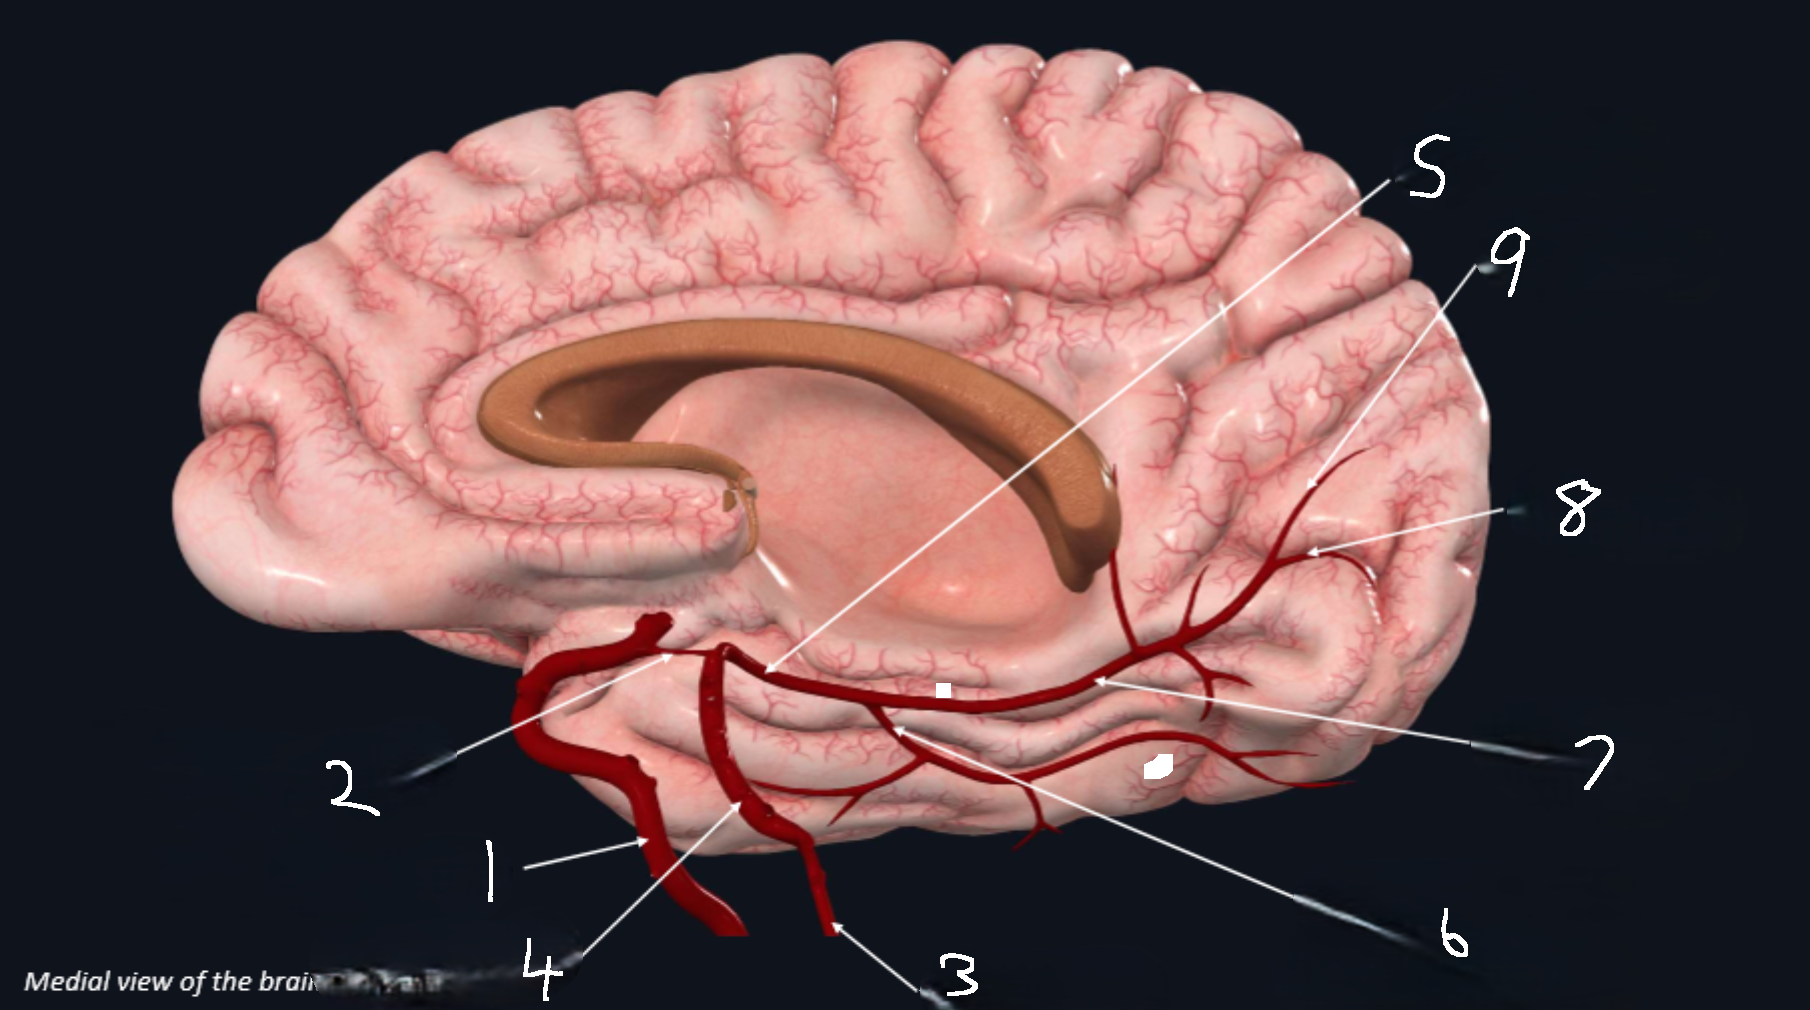

What is 1?

internal carotid artery

What is 2?

anterior cerebral artery

What is 3?

frontopolar artery

What is 4?

pericallosal artery

What is 5?

callosomarginal artery

What is 6?

corpus callosum